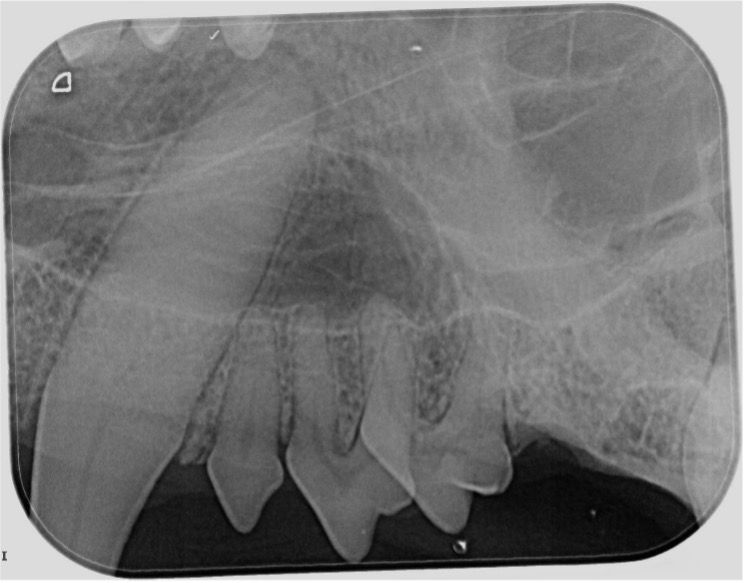

Routine spay or neuter exams offer a prime opportunity for oral health assessments, allowing early intervention for dental abnormalities. The team will assess crowding of teeth (Figure 5) that may allow PD to occur at a faster rate and visualize missing, fractured, displaced teeth causing trauma, and persistent deciduous teeth. This is a perfect time to advocate for baseline dental radiographs (Figure 6) and oral thiol tests to see what is happening under the gum line and decide when their first PRO may be needed.